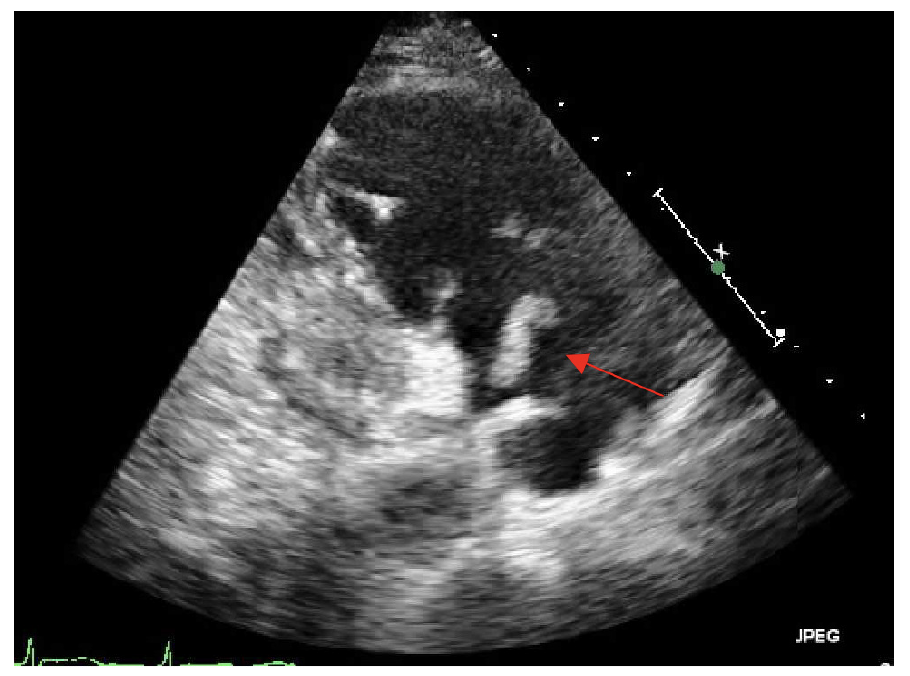

Transthoracic echocardiography showed severe dilated right chambers. There was a large, highly mobile right atrial thrombus (Figure 2), with severe systolic right ventricular dysfunction: severe tricuspid regurgitation and pulmonary artery systolic pressure of 100 mmHg (Figure 3).

Two types of RHT have been described. Type A thrombi are visualized in transit within the right cardiac cavities, morphologically serpiginous, highly mobile, and associated with PE. Type B thrombi are not mobile, formed in situ and are associated with underlying cardiac abnormalities. Based on the TTE images, this patient had a Type A thrombus.1,2,3